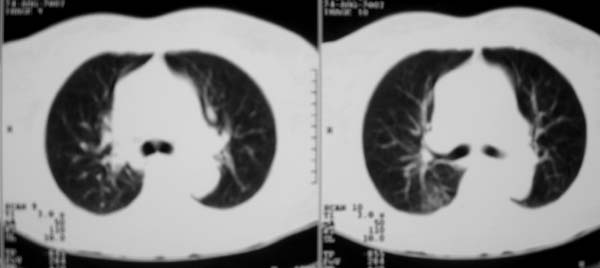

以下是引用zjzjr在2007-8-30 22:22:00的发言:[br]右上肺肺囊肿合并感染.右下肺肺大泡.左肺舌段感染.